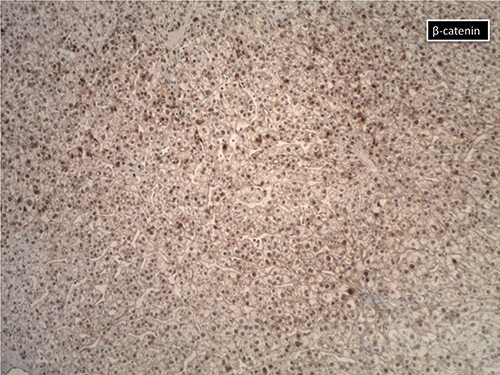

If an adenoma looks atypical, Dr. Richards said, it could be a beta-catenin mutated subtype. “Some American pathologists think that some of these lesions are actually already well-differentiated HCCs,” she says. “The difficulty comes when you try to use the beta-catenin stain [below] because it can be very, very focal” and can appear to be negative. Some pathologists have used strong glutamine synthetase overexpression as a surrogate. “There is always the risk in a biopsy,” however, Dr. Richards cautions, “that what appears to be diffuse overexpression is just oversampling of one area of a tumor that is more heterogeneous than represented on the biopsy.”